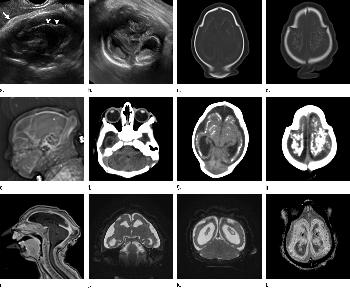

Figure 2. (a) Axial, (b) sagittal, and (c) coronal fetal T2-weighted MR images were obtained in a 29-year-old woman with confirmed Zika virus infection, initially seen for characteristic rash at 12 weeks of gestational age. (d) Axial postnatal CT image and (e–g) axial and (h) coronal T2-weighted MR images were obtained in her male neonate. The fetal MR images obtained at 34 weeks (a–c) show asymmetrical ventriculomegaly with a septation in the right occipital horn (arrowhead on a), small frontal lobes, thinning of the occipital parenchyma (left worse than right), underdeveloped sylvian fissures, and regions of thickened cortex, as in the right frontal lobe, which is suggestive of polymicrogyria (arrow on a). There is abnormal, increased signal intensity in the white matter. The postnatal CT image (d) obtained in the 22-day-old neonate shows punctate calcifications at the gray matter–white matter junction and asymmetrical ventriculomegaly. The T2-weighted MR images obtained at 26 days (e–h) show septation in the ventricle (arrowhead on e). Note how the right ventricle has relatively decreased in size compared with the prenatal image, whereas the left ventricle has increased in size. Under-rotation of the hippocampus (arrowheads on f) is demonstrated. There is clear asymmetry of the gyral pattern on g, which is relatively smooth in the left occipital region, with abnormal folds in the right occipital and frontoparietal regions (arrows on g). Subependymal cysts are visualized on h, which are not seen on fetal MR images.

High-res (TIF) version